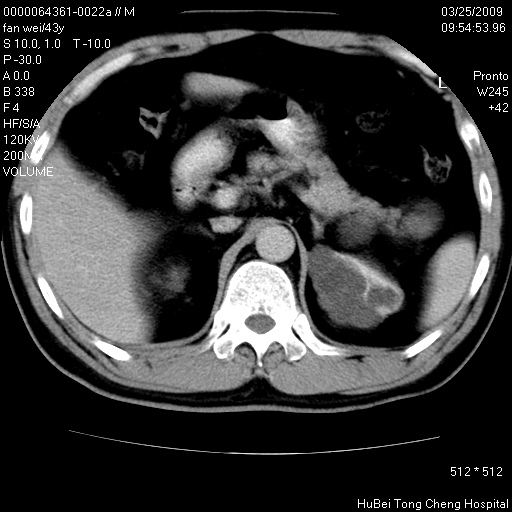

患者 男,43岁。左侧腰部不适两天。平素健康。无家族遗传病史。

腹部彩超提示:1)轻度脂肪肝。2)左肾多发囊性占位性病变;建议行进一步检查。

临床诊断:左肾多发囊性占位性病变,性质待定(多发肾囊肿?)。

双肾ct轴位平扫+增强扫描(层厚10mm,螺距1.0,重建间隔10mm),图像如下:

左肾体积变大,支持多囊肾。

双侧多囊肾!

双肾多发性囊肿   脂肪肝